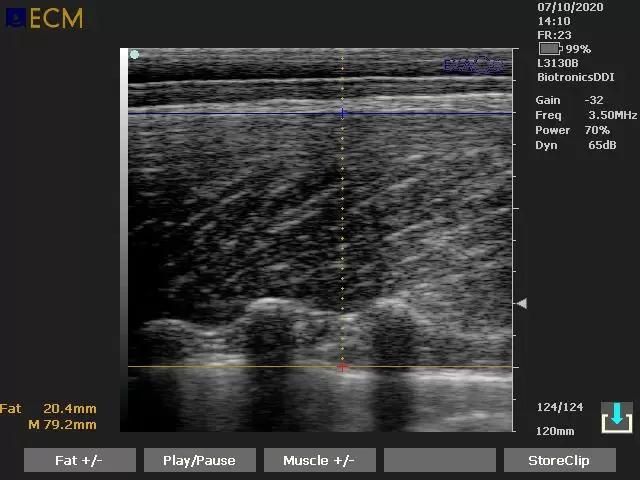

А теперь на примере снимка молодой свинки на стадии созревания

Большая часть изображения серая, видны некоторые затемнения, структуры плохо различимы, так как свинка ещё молодая и не осемененная. Небольшой белый отблик - стенка матки.

Справа- черного цвета - это мочевой пузырь.

Бывают ситуации когда мочевой пузырь наполнен - он отталкивает маточные трубы что затрудняет визуализацию, в таком случае лучше вернуться к данной свиноматке чуть позже, после его опорожнения.

Для большего удобства при работе с ремочками, необходимо размешать датчик чуть выше/ глубже.

Так как маточные связки ещё не растянуты вынашиванием плодов.